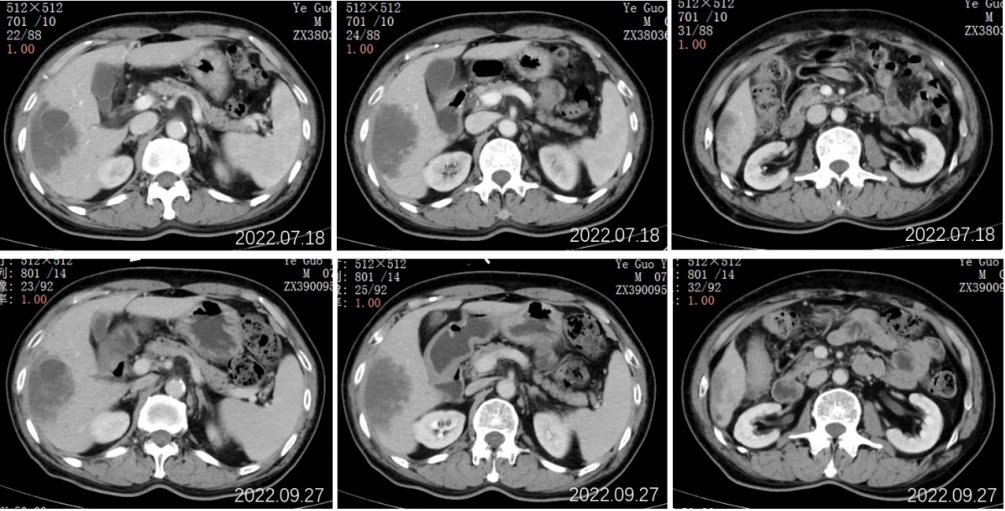

2022.07.19行全腹部平扫+增强:肝右叶可见一类圆形稍低密度影,累及肝S5-8段,边界欠清,约80mm*50mm*98mm大小,密度欠均匀,增强动脉期病灶边缘轻度强化,门脉期边缘环状强化更为明显,中心见无强化坏死区,病灶周围S6段另见数个小结节样类似强化灶;肝内另见数个类圆形低密度灶,径约7-25mm,增强扫描未见强化。

2022.09.27胸部CT平扫:1.两肺多发小结节、类结节影,较前相似,转移性考虑;2.两侧胸腔少量积液较前已吸收。3.左侧第5后肋骨质破坏。

2022.09.27腹部CT增强:肝胆管细胞癌治疗后复查:1、肝右叶多发占位,较前大小相仿,目前仍可见活性;2、肝内及双肾多发小囊肿,相仿;肝S2段小血管瘤考虑,相仿;3、慢性胆囊炎改变;4、肝内钙化灶;前列腺钙化灶。

2022.11.25腹部CT增强:肝胆管细胞癌治疗后复查:对比2022-09-27日:1、肝右叶多发占位,较前大小相仿,目前仍可见活性;2、肝内及双肾多发小囊肿,相仿;肝S2段小血管瘤考虑,相仿;3、慢性胆囊炎改变;4、肝内钙化灶;前列腺钙化灶。